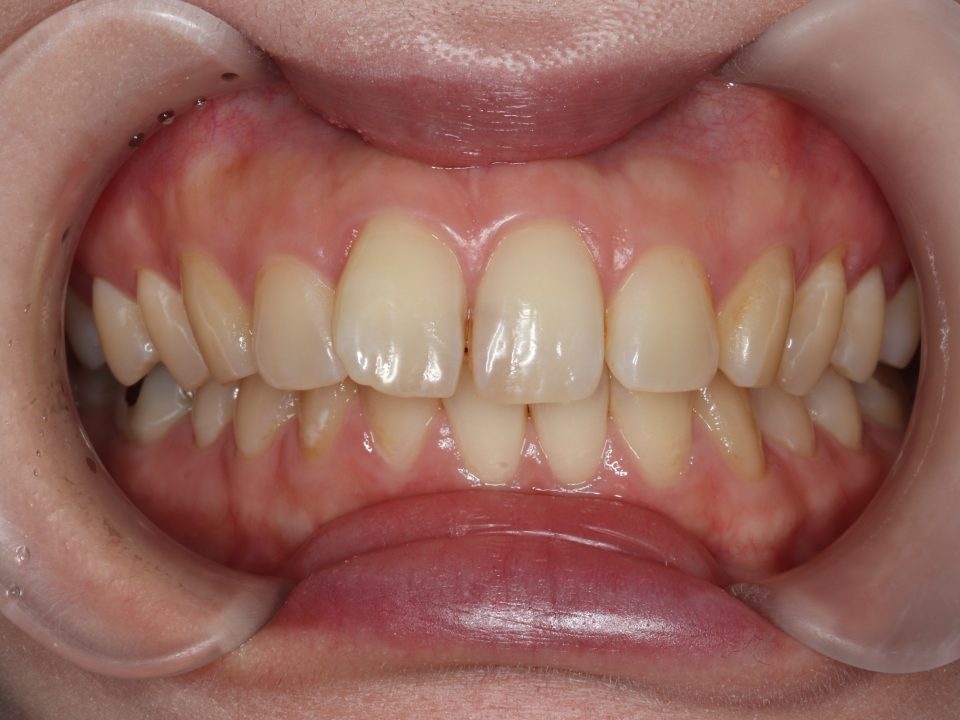

矯正治療前

20代女性の患者さんです。

右上前歯の捻じれと隙間を気にして来院されました。